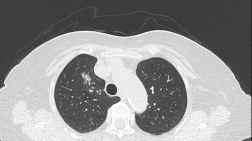

德陽首例!九旬高齡患者成功接受“Tubeless”胸腔鏡微創(chuàng)手術(shù)

近日,德陽市人民醫(yī)院心胸血管外科團隊成功為一名90歲高齡患者實施了“Tubeless”(無管化)單孔胸腔鏡下右肺上葉尖段切除+淋巴結(jié)清掃術(shù),這是德陽地區(qū)有史以來首例行“Tubeless”胸腔鏡微創(chuàng)手術(shù)患者年齡超過80歲的患者...